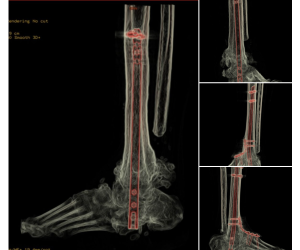

Progressive collapsing foot deformity with tibiotalar arthritis… a challenging problem

Jordan Sisto, DPM, FACFAS

Here we have a 69 y/o male with staged TAA on right that led to AVN talus and collapse which ultimately was revised to TTTA with great success -...